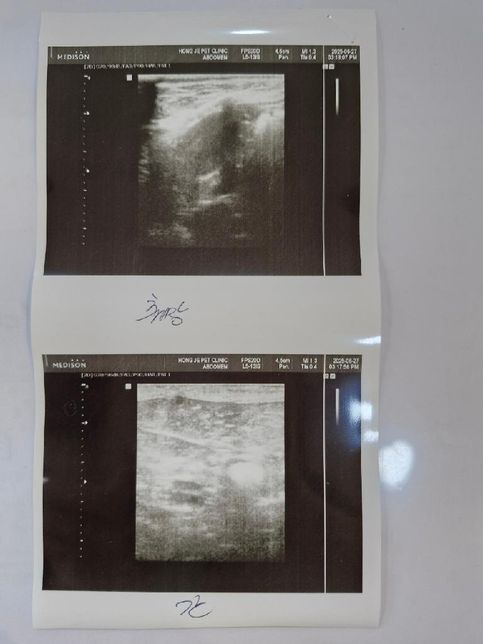

- 반려동물 건강반려동물Q. 어릴때 중성화 완료한 11살 수컷 전립선비대가 있습니다 전립선 그리고 방광 그리고 담낭좀 봐주시면 감사하겠습니다.현재 거의 포피염이 작년 9월경부터 낫지를 않고 있습니다.초음파는 예전에도 수차례 찍었지만 어떻게 우연히 전립선비대를 발견하게됬습니다.질문1) 전립선염이 있는지 방광염이 있는지 항생제를 먹어야할지 알려주세요.질문2) 담낭슬러지 우루사 어느정도 먹여야할정도인지.. (혈액검사상 담즙 흐름은 원활하다 합니다)단 한번도 우루사를 먹여 본적이 없습니다 질문3) 신장결석이 어느정도인지.. 알려주세요사진 순서대로 전립선 우측부신 좌측 신장 비장 방광 순입니다.